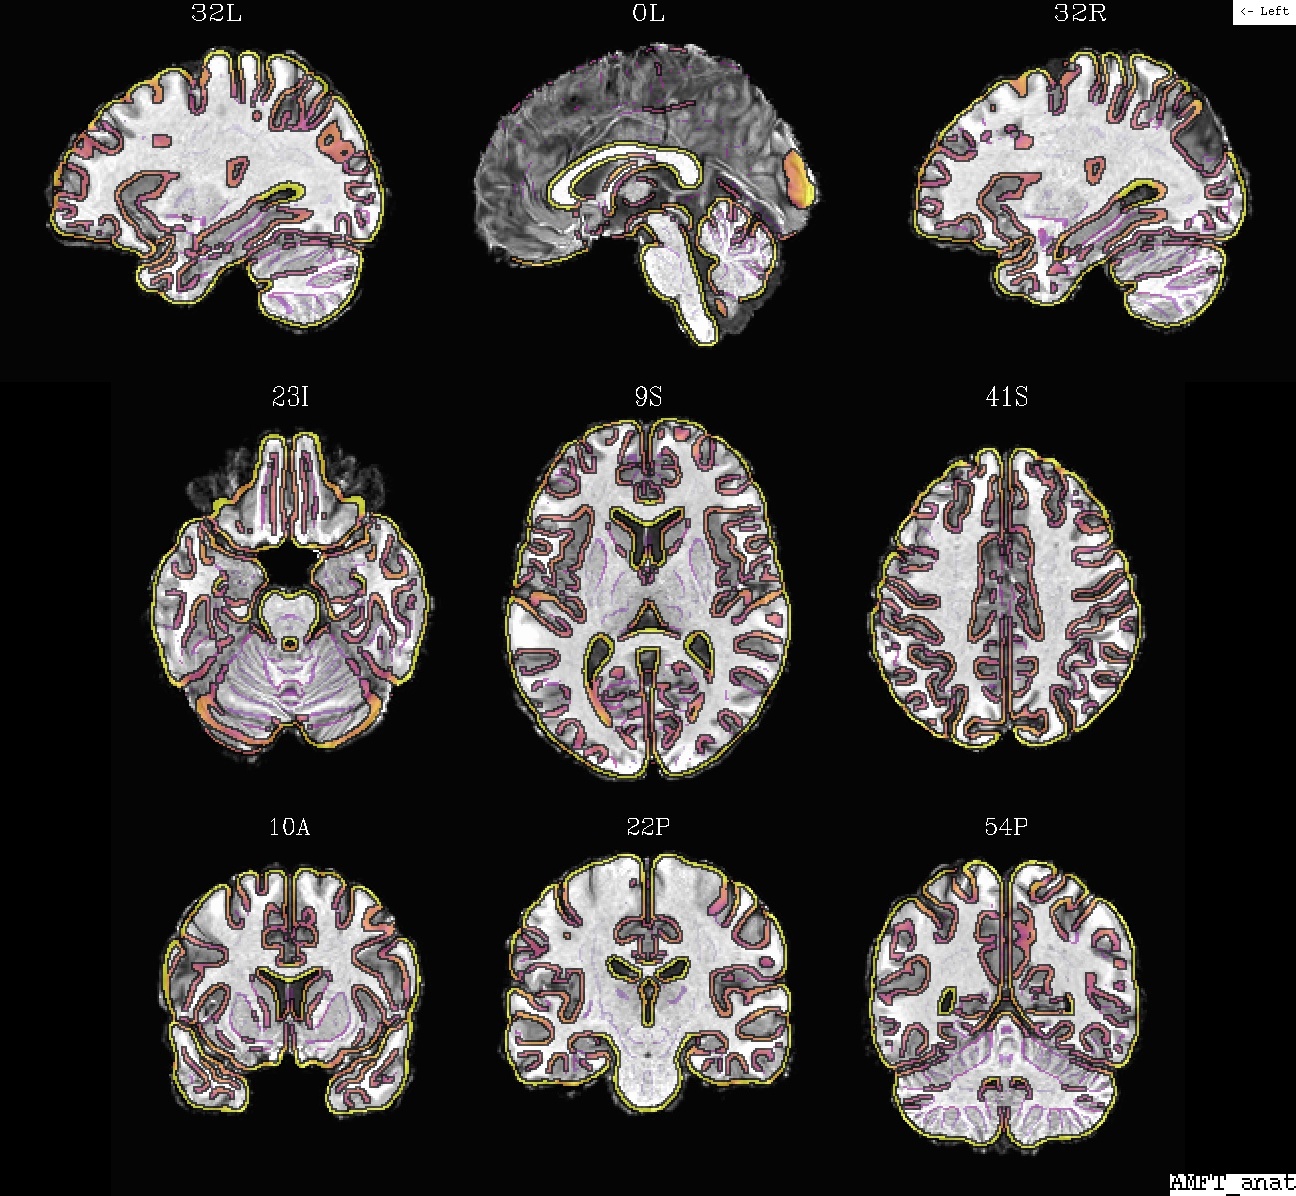

Example 5b: @SSwarper results (MA*.jpg), template (ulay) and anat, in template space |

|---|

|